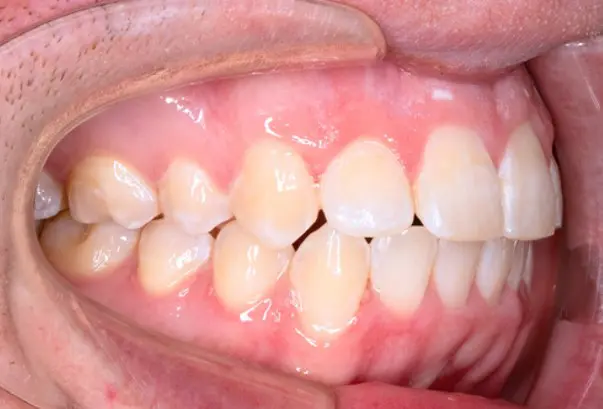

Crossbite/Uneven Bite

Before

After